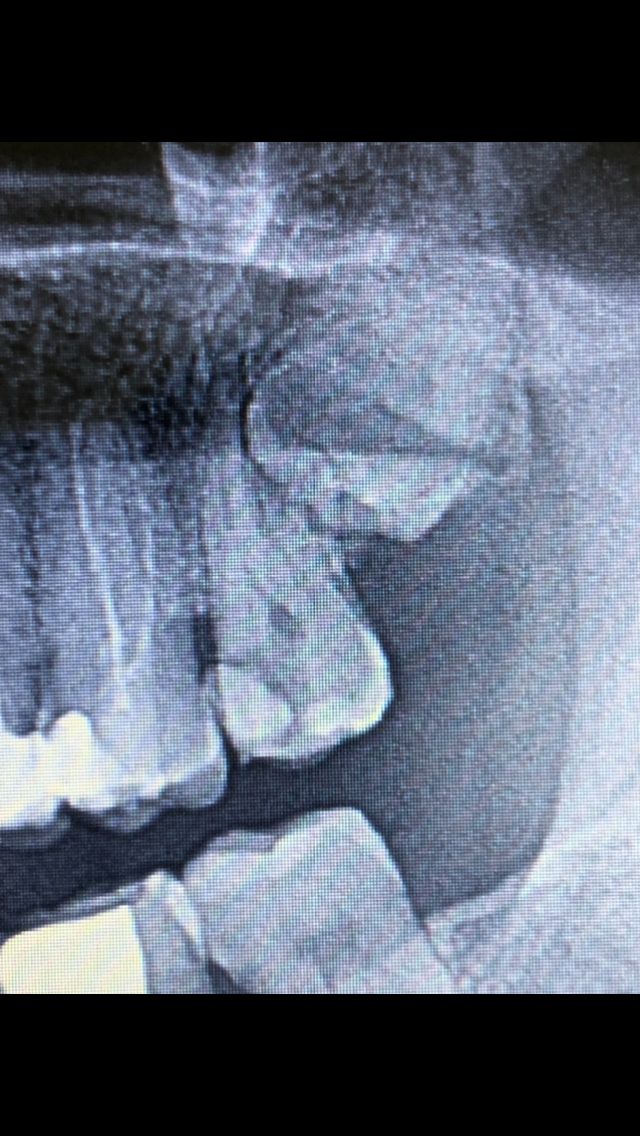

La raíz a palatina parece un poco de reabsorción lateral sin llegar al nervio:

A continuación rellenamos el conducto palatino con cemento de sellar (flecha en rojo) y vemos que se mantiene dentro del conducto sin esparcirse hacia fuera, esto nos tranquiliza, pues la rizólisis no llega a la luz del nervio. A continuación entró la gutapercha:

En último lugar hacemos la conductometría de la raíz distal vestibular que había sufrido la rizólisis, rellenamos con cemento sellador y a continuación entró la gutapercha. Y aquí si vemos que el cemento de sellar se desborda por apical de la raíz saliendo al exterior, queriendo esto decir que el nervio estaba afectado y no debíamos sobrepasarnos con la gutapercha (material de relleno). Terminados los rellenos de las tres raíces obturamos (relleno con composite) la pieza habiendo desaparecido totalmente el dolor. Paciente feliz.